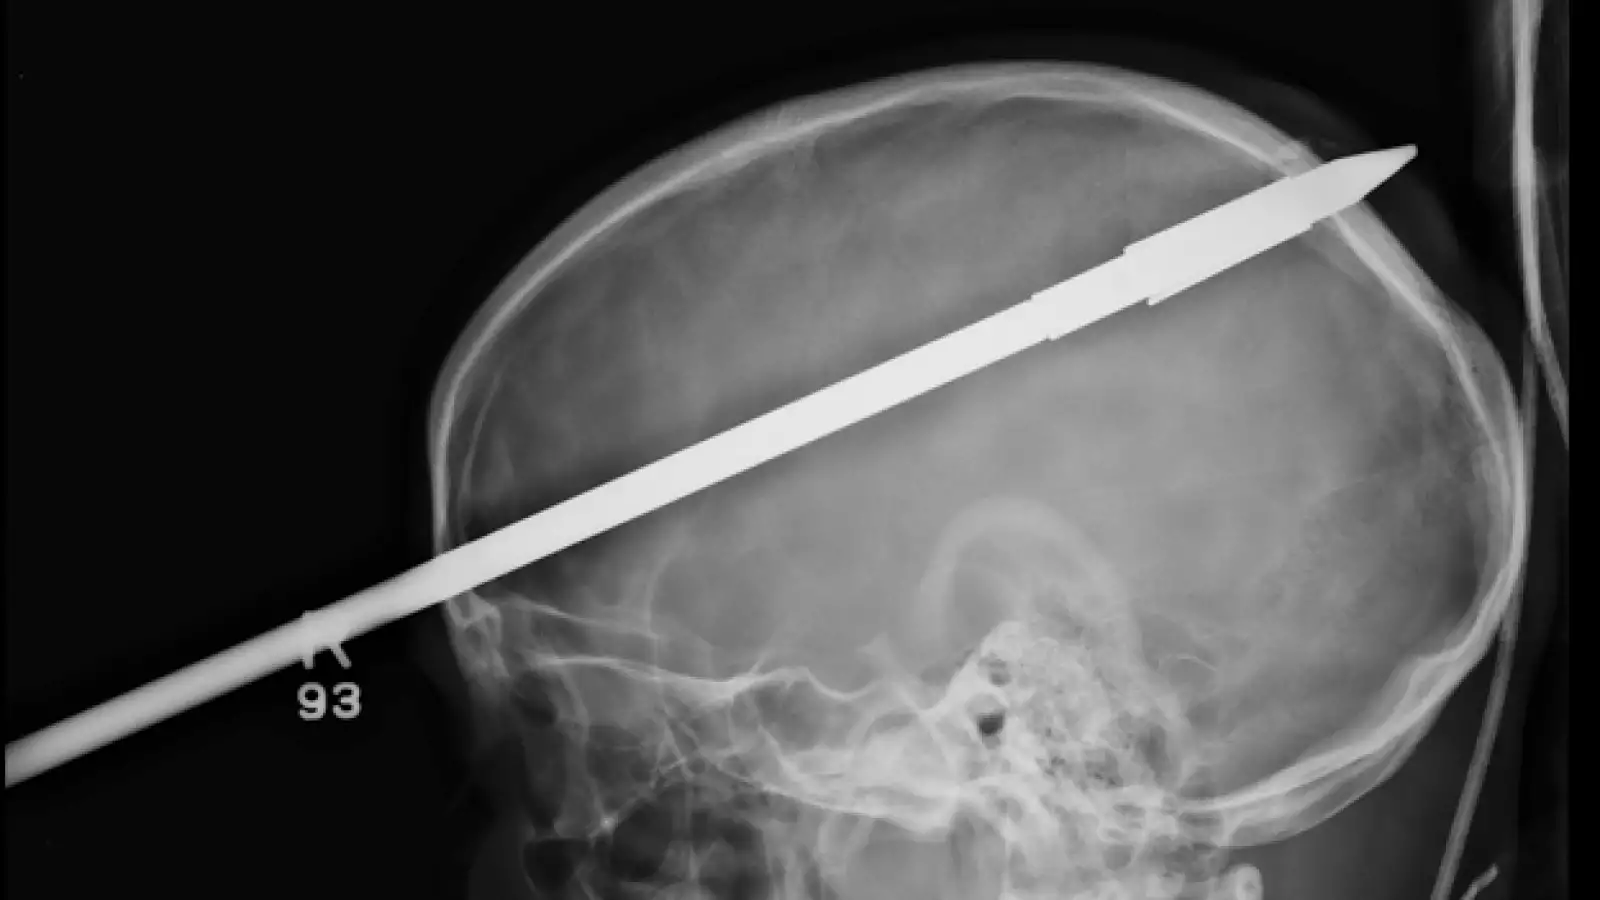

Un joven sobrevive luego de que un arpón de pesca atravesara su cráneo

Yasser López, logró sobrevivir después de que su amigo le disparara accidentalmente un arpón en un lago de Florida